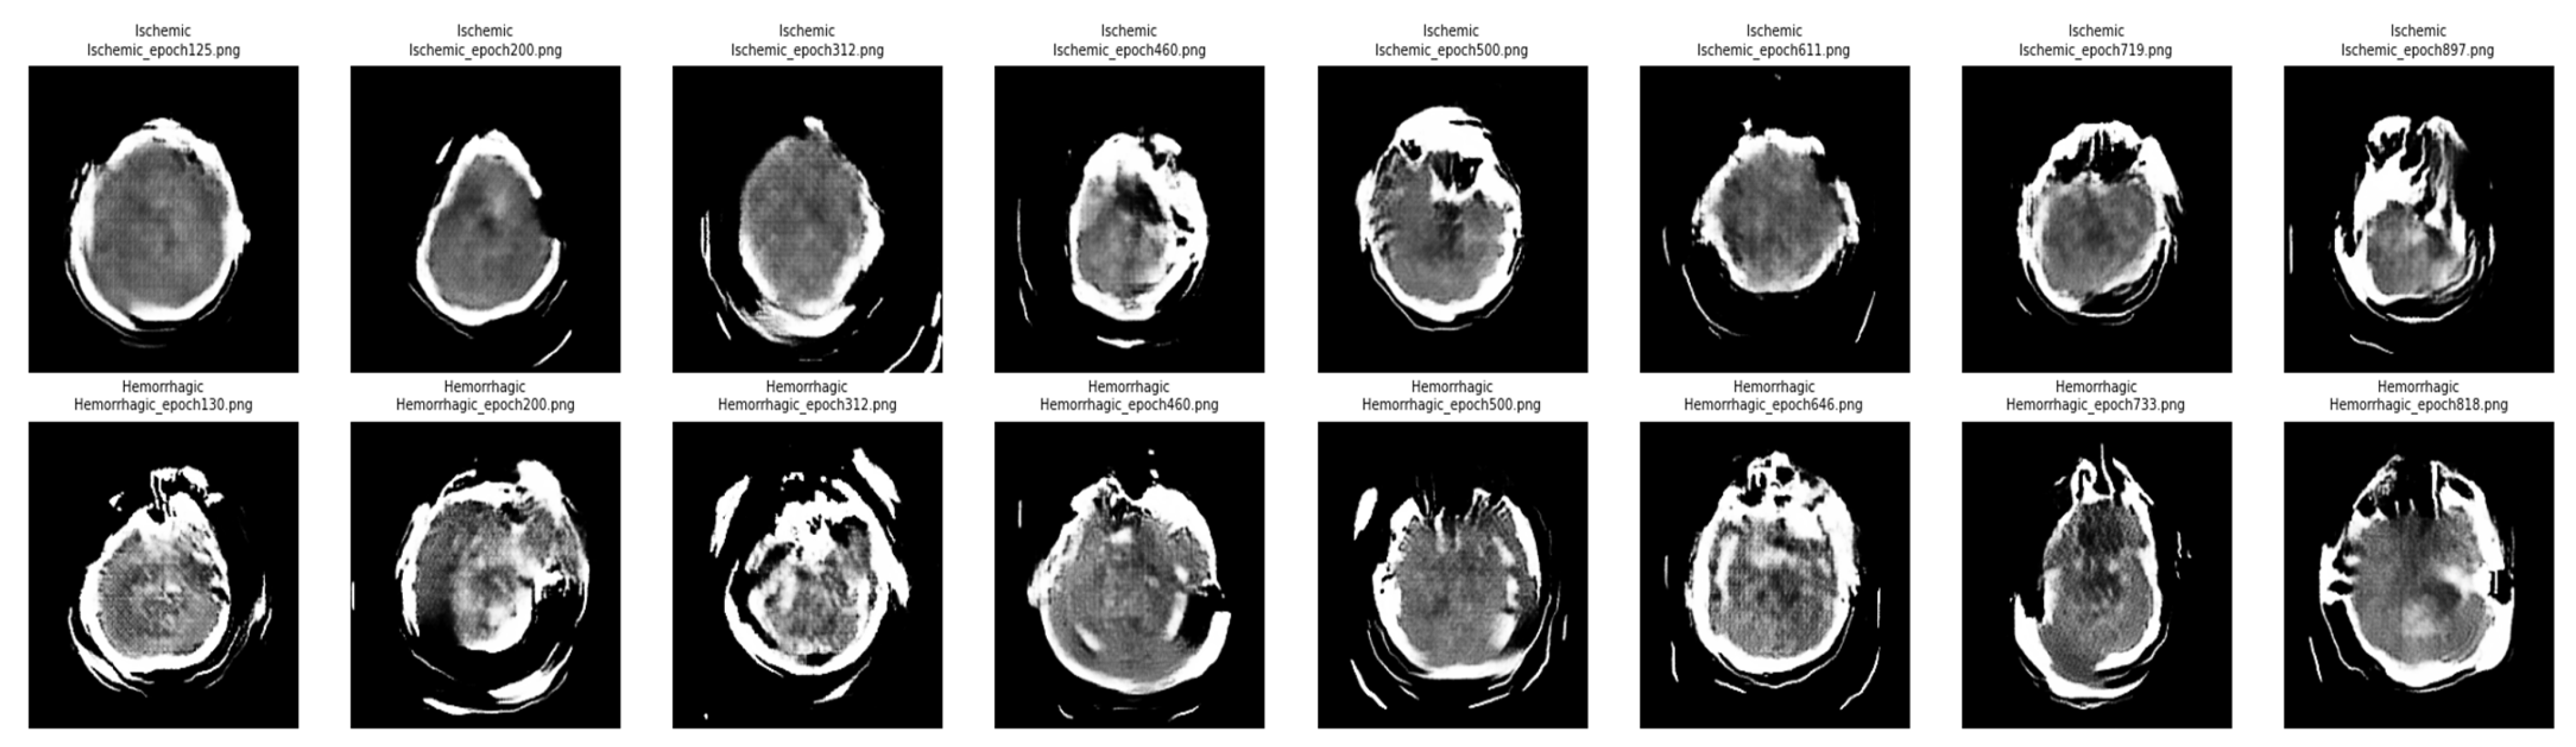

After completing the training, the quality of the generated images was assessed, showing significant similarity to the original CT scans. Based on this assessment, synthetic images for the Hemorrhagic and Ischemic categories generated during Phase 2 were integrated with the original training data for these two categories. No synthetic images were added for the Normal category to preserve class balance. As previously noted in Section 4.4, these synthetic images were used exclusively for training and were not included in the validation or test sets to ensure a fair evaluation. Figure 3 illustrates a sequence of synthetic CT images generated using the cGAN framework for both Ischemic (top row) and Hemorrhagic (bottom row) stroke classes. The images are captured at various training epochs, allowing visual examination of the model’s progression in learning crucial stroke features. The synthetic images from earlier epochs (such as epochs 125 and 130) show blurred anatomical structures, which suggest early-stage fluctuation and mode failure problems. Image quality improved significantly in later epochs (after 500 for Ischemic, and 664 for Hemorrhagic). Overall, the qualitative advancement demonstrates that cGAN effectively captures modality-specific stroke features.

Figure 3. Progressive synthetic CT-scan images generated by the conditional GAN (cGAN) for the Ischemic (top row) and Hemorrhagic (bottom row) stroke classes. Images in the leftmost columns (e.g., Epochs 125–130) show lower visual quality during early training, whereas images in the rightmost columns (e.g., Epochs 719–897) demonstrate improved anatomical structure and quality.